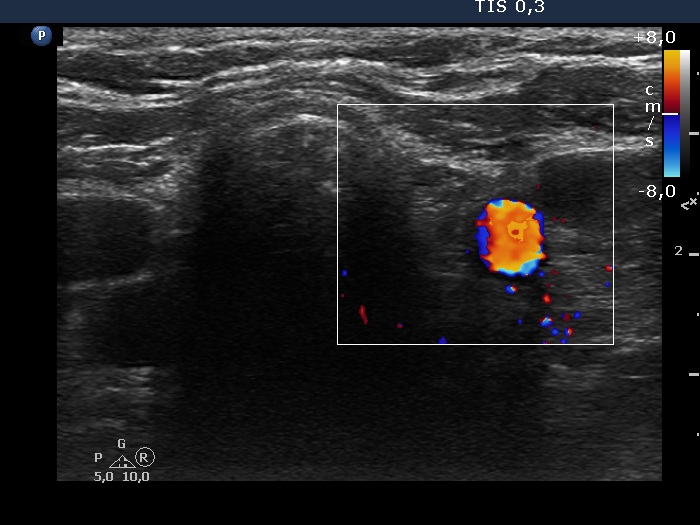

Right lobe, longitudinal scan

Left lobe, transverse scan, color Doppler mode. There is no vascularization in the thyroid bed.